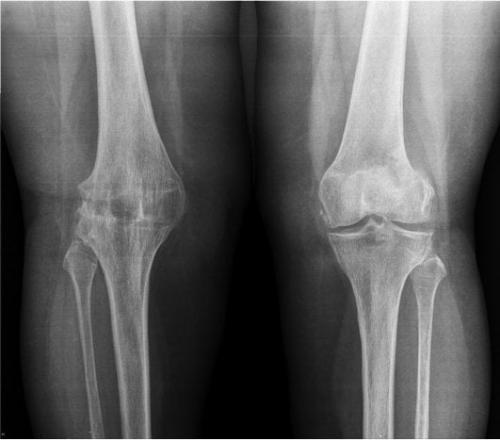

I стадия – при рентгенографии определяется незначительное сужение суставной щели по сравнению со здоровым суставом и лёгкий субхондральный остеосклероз. Клинически заболевание проявляется болью, возникающей после или при ходьбе, особенно, при спуске и подъёме по лестнице, которая проходит в состоянии покоя, иногда боль может появляться после долгого пребывания на ногах, движения в суставе, как правило, не ограничены;

II стадия – сужение рентгенологической суставной щели в 2–3 раза превышает норму, субхондральный склероз становится более выражен, по краям суставной щели и/или в зоне межмыщелкового возвышения появляются костные разрастания (остеофиты). Клинически – умеренный болевой синдром, развивается ограничение движений в суставе, гипотрофия мышц, хромота, определяется лёгкая фронтальная деформация оси конечности;

III стадия – клиническая картина характеризуется стойкими сгибательно– разгибательными контрактурами, резко выраженными болями и хромотой, умеренной и выраженной вальгусной или варусной деформацией конечности, нестабильностью сустава и атрофией мышц бедра и голени. При рентгенографии выявляется значительная деформация и склерозирование суставных поверхностей эпифизов с зонами субхондрального некроза и локального остеопороза, суставная щель почти полностью отсутствует, определяются обширные костные разрастания и свободные суставные тела.

Классификация Kellgren & Lawrence (рентгенологическая)

0 – отсутствие изменений

I – сомнительная: незначительные остеофиты;

II – минимальная: чётко выраженные единичные остеофиты и минимальное сужение суставной щели;

III – умеренная: умеренное сужение суставной щели и множественные остеофиты;

IV – тяжёлая: выраженное сужение суставной щели с субхондральным склерозом, грубые остеофиты.

Гонартроз коленного сустава 3 степени характеризуется утратой полноценного движения. Остаются только покачивания пораженным суставом. Он очень сильно деформируется. После рентгена можно увидеть отсутствие суставной щели. Сама поверхность расширена из-за разрастания ее краев. Деформирование остро выраженное, имеется уплотнение обоих эпифизов.

Артроз третьей степени характеризуется еще большим разрушением и истончением суставного хряща - менее 1,2 мм (норма 2,5-2,7мм). Суставная щель резко сужена, деформация сустава хорошо заметна. В самом суставе появляются множественные остеофиты и воспалительная жидкость.

Анкилоз правого колена(на изображении слева).